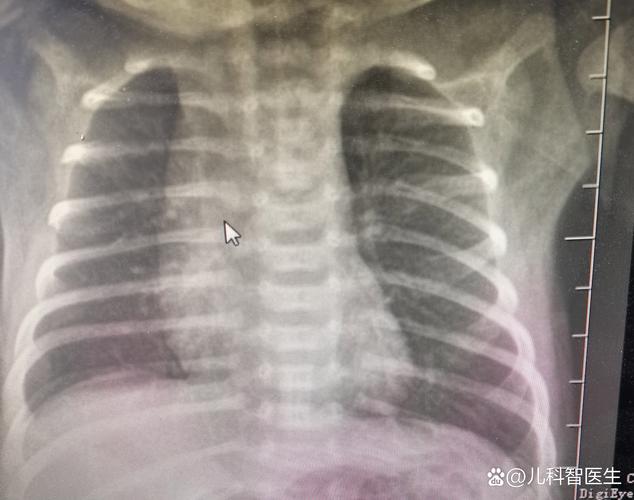

新生儿肺透明膜病的X线表现具有特征性,主要反映了肺泡萎陷、肺泡管和终末细支气管扩张以及支气管充气征的病理生理改变,其严重程度与病程进展密切相关,因此X线检查不仅是诊断的重要依据,也是评估病情和指导治疗的关键手段。

典型的X线征象

肺野呈“毛玻璃”样改变

这是疾病早期或轻度的典型表现。

- 成因:广泛的肺泡萎陷导致肺的含气量显著减少,而肺泡管和终末细支气管因过度扩张而充满了空气,这两者形成了密度不均匀的影像,透过这层“不均匀的肺”可以看到含气的肺血管影,整体外观如同磨砂玻璃或毛玻璃。

- 特点:肺野透亮度普遍性降低,但并非完全均匀一致,内部可见模糊的网状或颗粒状结构。

支气管充气征

这是最具特征性的X线征象,在毛玻璃背景上尤为明显。

- 成因:由于肺泡萎陷塌陷,而中央的气管、支气管分支仍保持通畅并充满空气,在密度增高的肺野衬托下,这些充气的支气管树分支被清晰地勾勒出来,形成“树枝状”或“轨道状”的影像。

- 特点:从肺门向外延伸的、分支状的透亮影,在毛玻璃样或白色的肺背景下非常醒目。

“白肺”

这是疾病发展到严重阶段的表现。

- 成因:肺泡萎陷范围极广,肺实质几乎完全失去气体,被渗出物(透明膜)和水肿液填充,肺动脉压力增高可能导致肺水肿,进一步加重肺实变。

- 特点:整个肺野呈均匀致密的白色,心影轮廓和膈面边缘变得模糊不清。支气管充气征可能仍然存在,是诊断的重要线索。

X线表现的动态演变与分级

HMD的X线表现是一个动态变化的过程,临床上常根据其严重程度进行分级,有助于评估病情和指导治疗(如是否需要呼吸机支持)。

| I 级 (Grade I) | 肺内广泛颗粒状、网状阴影,肺透亮度轻度降低,可见支气管充气征。 | 轻度HMD,可能仅需CPAP(持续气道正压通气)支持。 |

| II 级 (Grade II) | 肺野呈典型的“毛玻璃”样改变,支气管充气征清晰可见,心脏和膈肌轮廓尚可辨认。 | 中度HMD,通常需要CPAP或机械通气。 |

| III 级 (Grade III) | 肺野大部分呈“白肺”,支气管充气征非常明显,心脏边缘开始模糊。 | 重度HMD,需要强有力的机械通气支持。 |

| IV 级 (Grade IV) | 整个肺野完全“白肺”,支气管充气征可能因过度充气或肺实变而变得不明显,心影和膈肌轮廓完全消失。 | 极度严重,常合并气胸、肺出血等并发症,预后极差。 |

新生儿肺透明膜病的X线表现是一个从颗粒状阴影 → 毛玻璃样改变 → 白肺的动态演变过程,支气管充气征贯穿其中,是其最具特征性的标志,放射科医生和临床医生通过分析这些X线征象的严重程度和动态变化,能够快速准确地诊断HMD,评估病情,并为制定呼吸支持方案(如是否使用肺表面活性物质PS)提供关键的影像学依据。